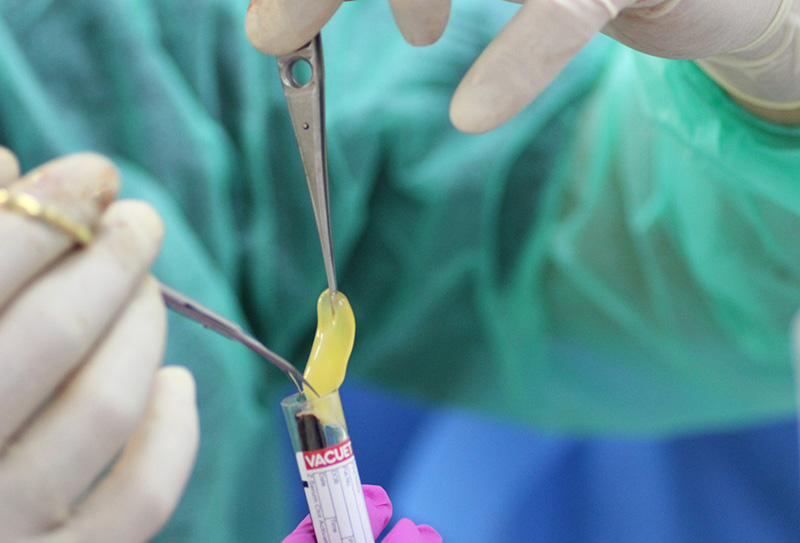

Мастер-Класс «Одномоментная Имплантация С Аугментацией Кости», с использованием имплантатов Alfa Gate

25-ого октября в учебном центре Стом-Лайн был проведен мастер-класс на тему «Одномоментная имплантация с аугментацией (наращиванием) кости, с использованием имплантатов Alfa Gate Dental Implants». Мастер-класс провел главный врач-стоматолог клиники «Нюанс» в Москве Мхитар Казарян.

Мастер-класс начался с обсуждения предстоящей операции и исследования компьютерной томографии, после чего участники смогли присутствовать на операции или следить за ней из учебного центра.